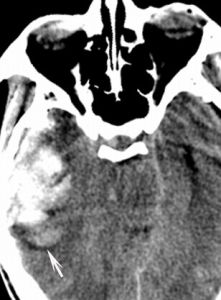

2.CT

為首選檢查方法,可用於:①顯示挫裂傷的部位、程度和有無繼發性出血和水腫等表現,根據腦室和腦池的大小和形態間接評估顱內壓的高低,必要時需反覆多次CT掃描,以動態觀察腦水腫的演變並發現遲發性顱內血腫。②腦挫傷的CT表現為低密度腦水腫中出現多發散在的斑點狀高密度出血灶,腦室受壓移位等。③常伴隨蛛網膜下腔出血,表現為廣泛的蛛網膜下腔和腦池,甚至腦室出現高密度影,以大腦縱裂出血的條索狀窄高密度影最常見,尤其在兒童患者更為明顯。④瀰漫性腦損傷常表現為腦水腫和腦腫脹,CT表現為普遍性密度減低。⑤高分辨CT對小區域的腦幹損傷診斷仍有困難。